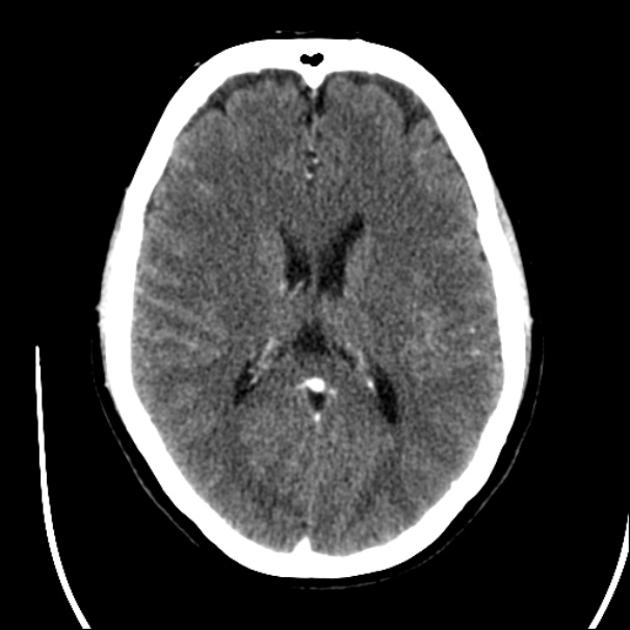

Normal CT👇